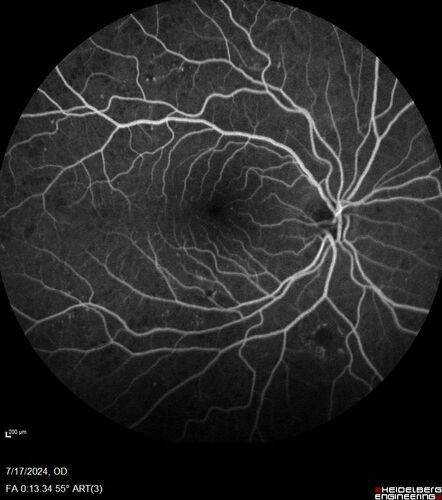

Bear tracks (and diabetic retinopathy)

48 year old female with bear tracks in her retina and NPDR.

Bear tracks (in an eye with diabetic retinopathy)